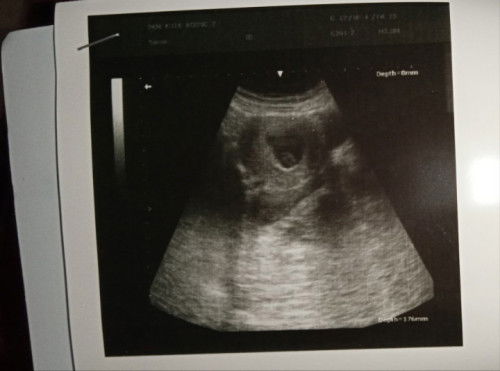

8w2d Belum ada janin, USG di puskesmas

Ada yang sama juga gak ya dengan saya seperti ini ceritanya. Tadi saya USG pertama kali di puskesmas, kata nya belum ada janinnya. Baru kelihatan kantong rahim sama gumpalan darah saja baru. Jadi saya overthinking, bunda" ada pengalaman yg sama ga ya?? Semoga beberapa minggu lagi janinnya sudah ada ya Allah. Dan janinnya sehat kuat sampai waktunya lahir, dengan wujud dan rupa yang sempurna tanpa kurang satupun. Serta bakal cikal anak yg sholeh berbakti dengan ortu dan bermanfaat untuk sesama.